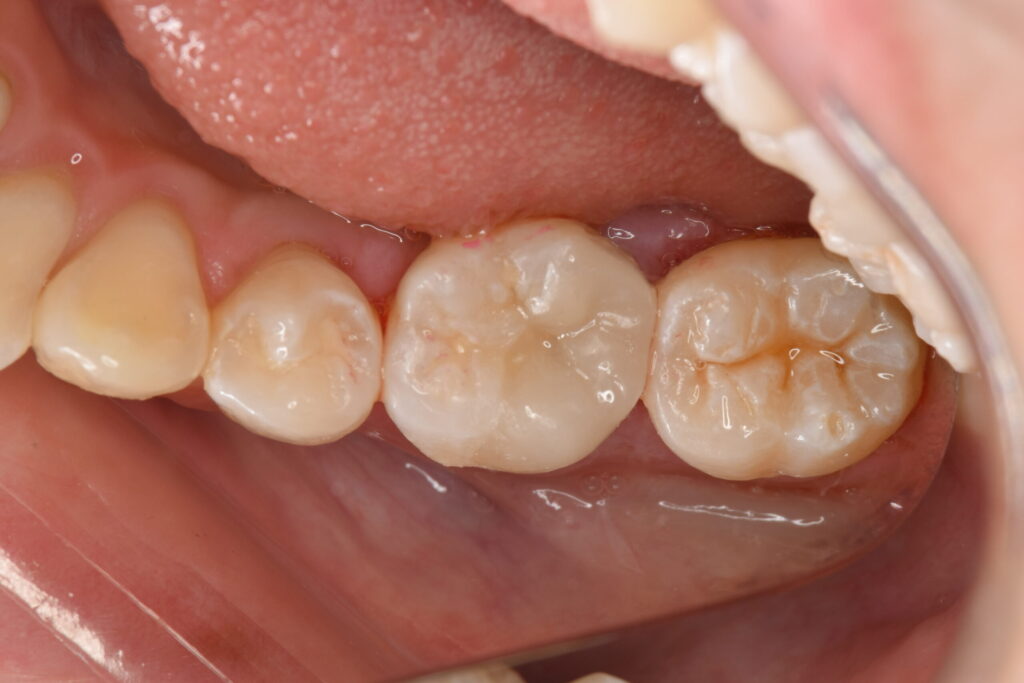

ラバーダム防湿下でセラミックオーバーレイ(テーブルトップベニヤ)を接着しました。

白丸の範囲、隙間が全くないことがわかります。

隙間を作らないことで汚れや細菌が入るスペースを与えず、虫歯の再発予防に寄与すると考えられます。

オーバーレイ(テーブルトップベニヤ、またはアンレー)は、特に奥歯の咬合面(噛み合わせる面)を中心に修復する治療法です。その最大の特長は、クラウン(被せ物)のように歯全体を削る必要がなく、健康な歯質を最大限に温存できる点にあります。これにより、歯の構造的な強度を保ち、歯の寿命を延ばすことに貢献します。また、セラミックなどの材料を用いることで、天然歯に酷似した色調と透明感を再現し、高い審美性を実現します。精密に作製されたオーバーレイは、噛む力を適切に分散させ、長期的な機能と安定性をもたらす、歯を大切にするための治療法です。